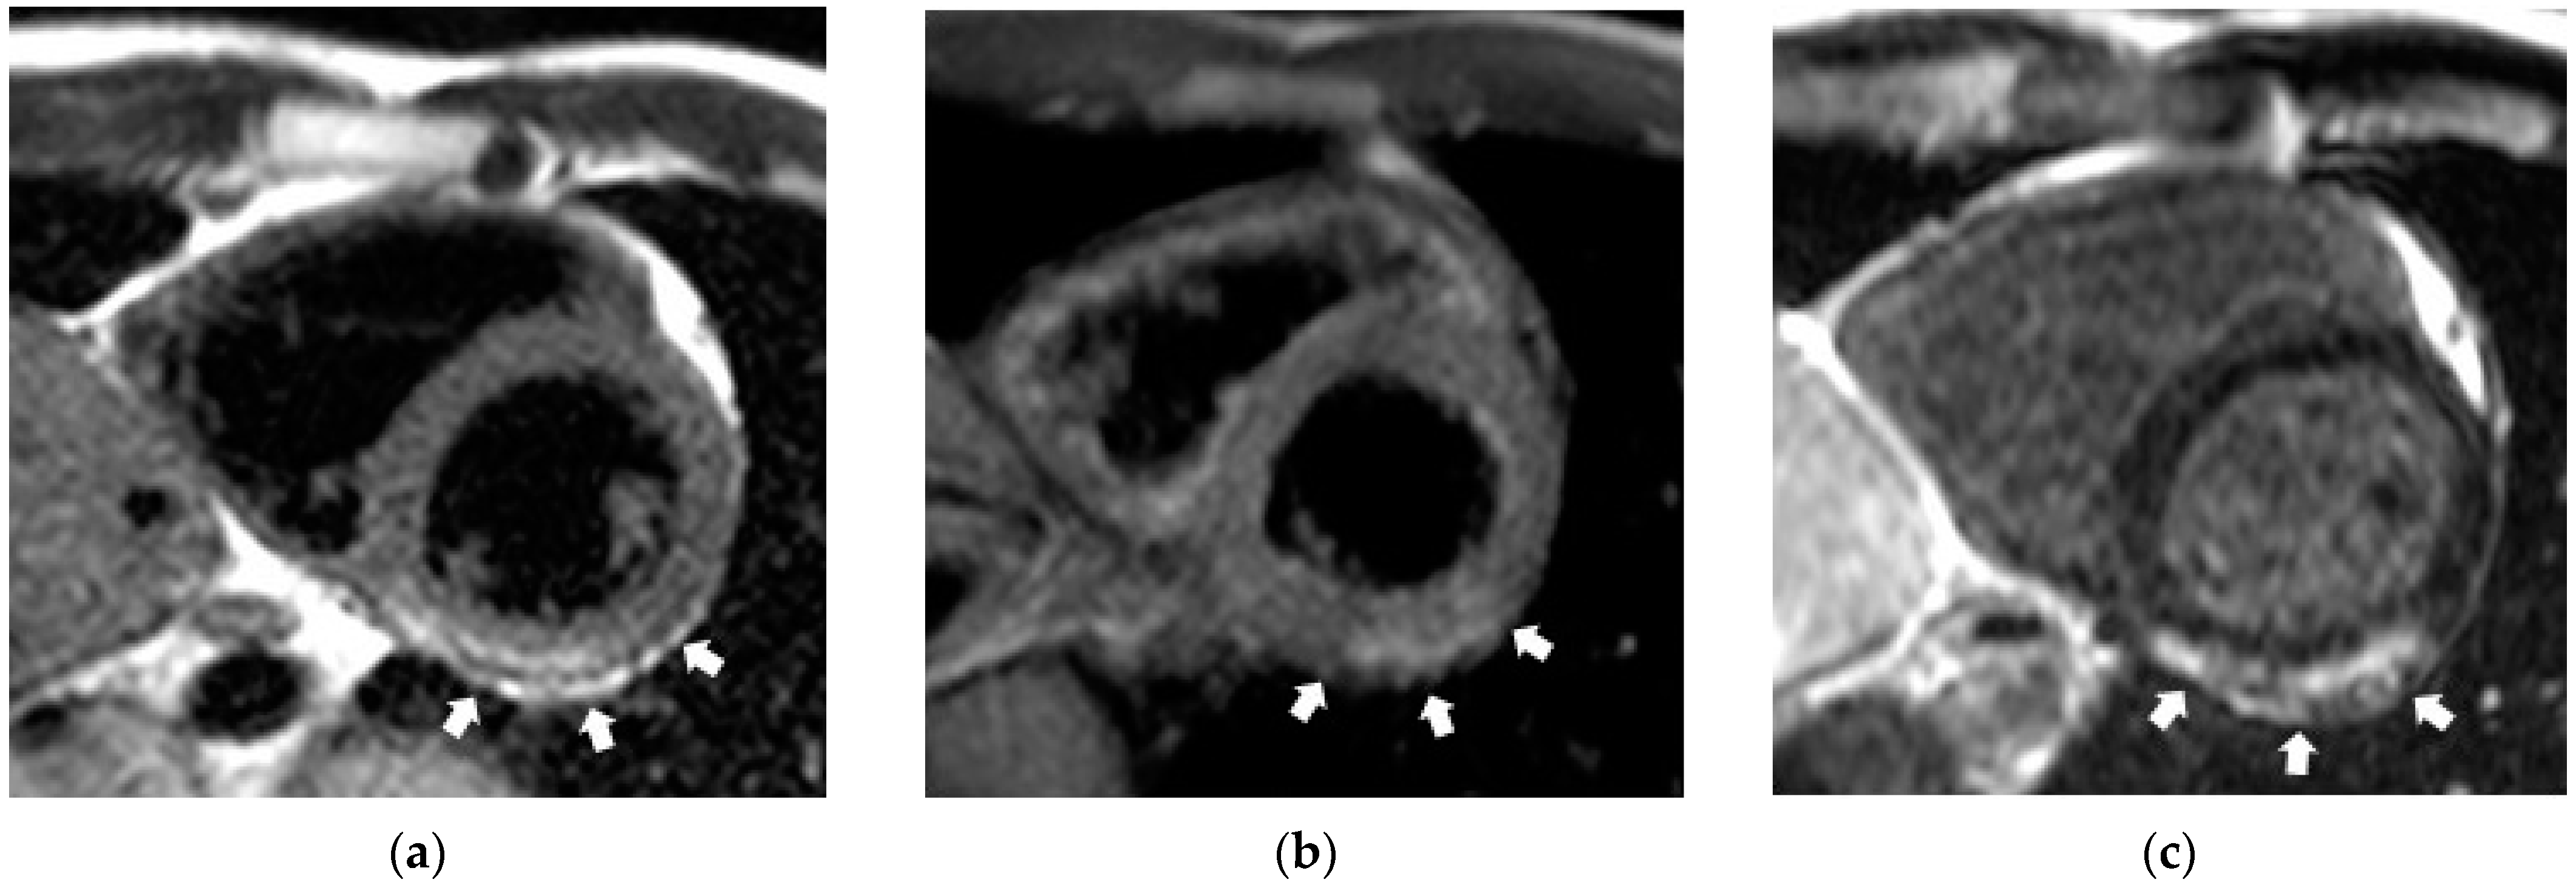

3.5. CE-CMR-Detected Non-Coronarogenic Myocardial Fibrosis during COVID-19 Pandemic

- Shelkovnikova, T.A.; Pushnikova, E.Y.; Baev, A.E.; Ryabov, V.V.; Ussov, W.Y. Magnetic resonance syndromes of myocardial damage in patients after new coronavirus infection (COVID-19)—Two typical clinical cases. Sib. J. Clin. Exp. Med. 2022, 37, 135–141. (In Russian) [Google Scholar] [CrossRef]